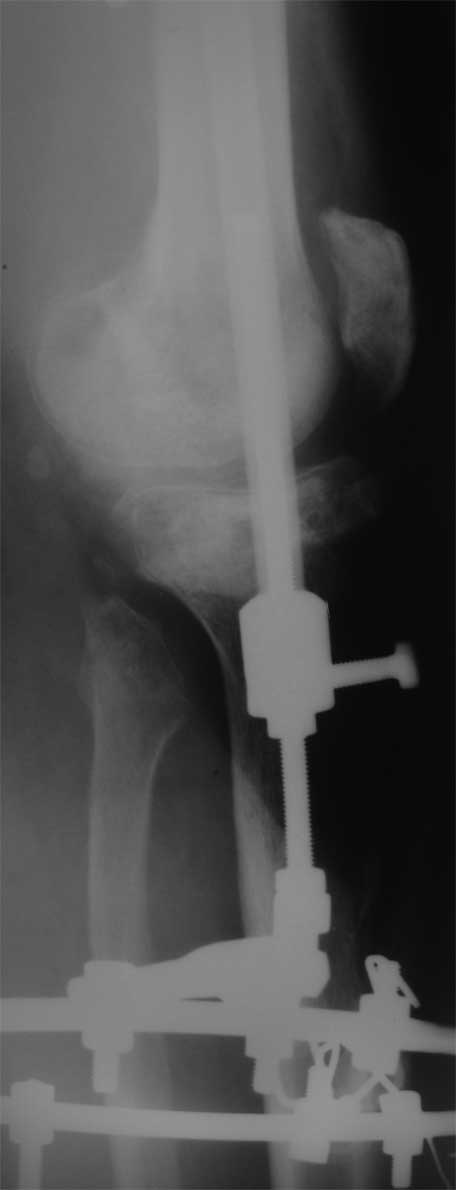

Я бы сделал пластику мягких тканей (торакодорзальный лоскут совместно с микрохирургами или пластику латеральной головкой икроножной мышцы) и выполнил бы краевой отщеп большеберцовой кости для его дистракции аппаратом в проксимальном направлении (рис. 1 – пример применения отщепа (авторство не мое), рис. 2 – схема предлагаемого варианта замещения дефекта кости).

Малоберцовую кость я бы пока не трогал. Она сослужит хорошую службу при начале нагрузки на ногу - будет служить дополнительным стабилизирующим и элементом.